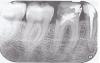

x3m Опубликовано 25 ноября, 2010 Поделиться Опубликовано 25 ноября, 2010 (изменено) ... и то, подлежит перелечиванию - если нет глубокого кариеса корня на уровне кости.другими словами - лечение и протезирование будет нецелесообразным, если кариес съел корень чересчур глубоко.вот те места, о которых я говорю:http://i037.radikal.ru/1011/ae/cc3f79ce7eb3.jpgкрасным обозначены: уровень кости и уровень разрушения зуба.пунктир в 5 зубе - возможный уровень разрушения (хотя больше похоже на контур кости). Надо бы еще вживую посмотреть. Изменено 25 ноября, 2010 пользователем x3m Ссылка на комментарий

mirexes Опубликовано 25 ноября, 2010 Поделиться Опубликовано 25 ноября, 2010 (изменено) Это в бесплатной клинике говорят? Скорее всего...Сходите в хорошую,частную. Я ничего страшного не разглядела,думаю,стоит пытаться лечить. Пятый перелечивать нужно. А в области 6 бифуркации вас ничего ненастораживает? Изменено 25 ноября, 2010 пользователем mirexes Ссылка на комментарий

Bier Опубликовано 25 ноября, 2010 Поделиться Опубликовано 25 ноября, 2010 А в области 6 бифуркации вас ничего не настораживает?да вроде как нет. Ссылка на комментарий

mike1982 Опубликовано 26 ноября, 2010 Автор Поделиться Опубликовано 26 ноября, 2010 (изменено) ... и то, подлежит перелечиванию - если нет глубокого кариеса корня на уровне кости. А как понимать если нет глубокого кариеса корня на уровне кости? Это там где красные черточки? И если есть глубокий кариес то уже ничего сделать нельзя? Изменено 26 ноября, 2010 пользователем mike1982 Ссылка на комментарий

pawa Опубликовано 26 ноября, 2010 Поделиться Опубликовано 26 ноября, 2010 И если есть глубокий кариес то уже ничего сделать нельзя?Можно, но это еще несколько удорожит стоимость лечения. В ГСП этим не занимаются. Ссылка на комментарий